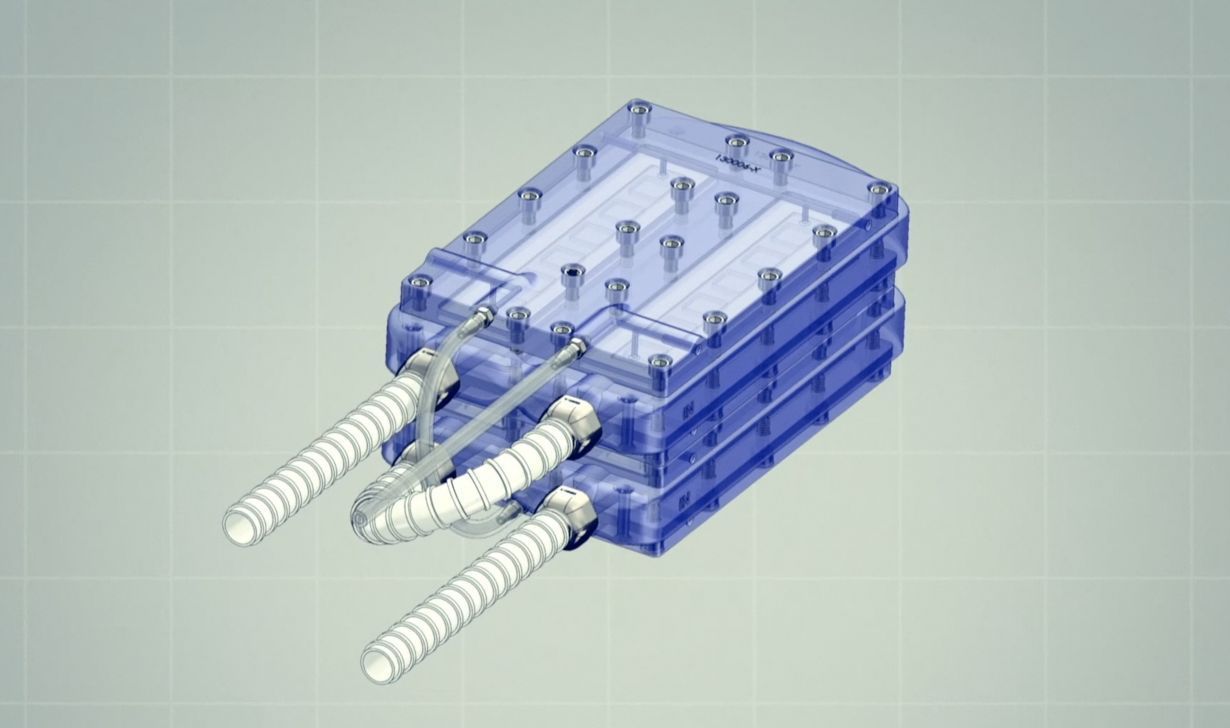

🩸 Konstgjord njure kan ersätta dialys

En konstgjord njure som inte är större än en vanlig njure och som inte behöver någon extern kraftkälla kan snart ge många möjlighet att få en ny njure.